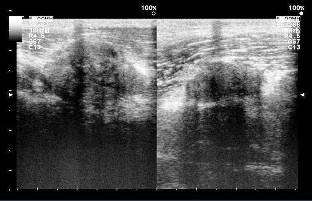

Ultrasonido articular y partes blandas, observándose imagen compleja en proyección de los músculos gastronemios con zonas solidas que alternan con imágenes quísticas tabicadas. Imágenes 5, 6 y 7

Imagen 5. Ultrasonido articular con imagen compleja

Imagen 6. Ultrasonido articular y partes blandas con zonas solidas que alternan con imágenes quísticas tabicadas

Imagen 7. Otra vista del ultrasonido articular que muestra zonas solidas que alternan con imágenes quísticas